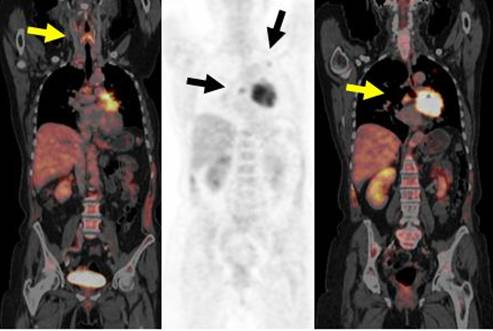

FDG PET-CT showed intense uptake in a big mass in the left upper lobe, with multiple lymphonodes in the left hilum and mediastinum (Coronal slices, left and right images are fusion of PET and CT). Two of them are in the right side, one under the carina with marked glucose metabolism (arrows, in middle and right slices). Study was consistent with non small lung carcinoma with metastasis to the right hilum lung and contralateral mediastinum. Though, the tumor is confined to the thorax, surgery was not performed due to the contralateral involvement. Yellow arrow in the left slice points to a normal larynx and uptake in the phonation muscles.